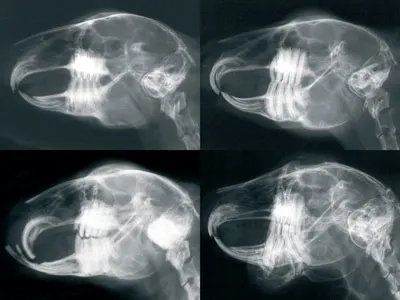

ImagingDental radiology is critical for evaluating tooth roots, staging dental disease, and determining the degree of overgrowth (Figure 2). Radiographs taken after a procedure help determine whether correction or reduction is adequate. Five views are required for complete evaluation: lateral, right oblique, left oblique, dorsal/ventral or ventral/dorsal, and rostral/caudal. Dental radiographs must be of excellent quality in terms of both technique and positioning. Computed tomography of the skull is extremely useful to help characterize dental disease in rabbits.

Figure 2

Featured Image